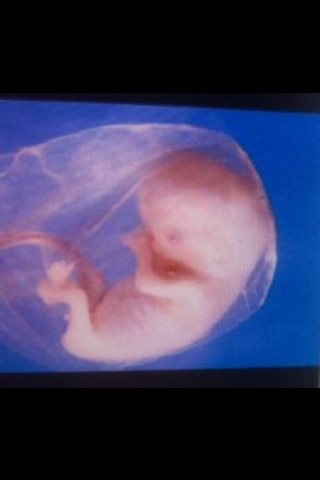

Se forman cavidades y se forman sus orejas y ojos

se van formando las cavidades para los riñones, musculos, pulmones y sistema digestivo

Su corazón late con una medida de 150 pulsaciones por minuto